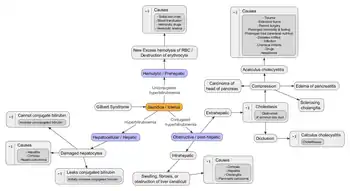

Jaundice is a sign indicating the presence of an underlying diseases involving abnormal bilirubin metabolism, liver dysfunction, or biliary-tract obstruction. In general, jaundice is present when blood levels of bilirubin exceed 3 mg/dl.[14] Jaundice is classified into three categories, depending on which part of the physiological mechanism the pathology affects. The three categories are:

| Prehepatic/hemolytic | The pathology occurs prior to the liver metabolism, due to either intrinsic causes to red blood cell rupture or extrinsic causes to red blood cell rupture. |

| Hepatic/hepatocellular | The pathology is due to damage of parenchymal liver cells. |

| Posthepatic/cholestatic | The pathology occurs after bilirubin conjugation in the liver, due to obstruction of the biliary tract and/or decreased bilirubin excretion.[21] |

Prehepatic causes

Prehepatic jaundice is most commonly caused by a pathological increased rate of red blood cell (erythrocyte) hemolysis. The increased breakdown of erythrocytes → increased unconjugated serum bilirubin → increased deposition of unconjugated bilirubin into mucosal tissue.[22] These diseases may cause jaundice due to increased erythrocyte hemolysis:[23]

Hepatic causes

Hepatic jaundice is caused by abnormal liver metabolism of bilirubin.[27] The major causes of hepatic jaundice are significant damage to hepatocytes due to infectious, drug/medication-induced, autoimmune etiology, or less commonly, due to inheritable genetic diseases.[28] The following is a partial list of hepatic causes to jaundice:[29]

Posthepatic causes (Obstructive jaundice)

Posthepatic jaundice (obstructive jaundice) is caused by a blockage of bile ducts that transport bile containing conjugated bilirubin out of the liver for excretion.[30] This is a list of conditions that can cause posthepatic jaundice:

Pathophysiology

Jaundice is typically caused by an underlying pathological process that occurs at some point along the normal physiological pathway of heme metabolism. A deeper understanding of the anatomical flow of normal heme metabolism is essential to appreciate the importance of prehepatic, hepatic, and posthepatic categories. Thus, an anatomical approach to heme metabolism precedes a discussion of the pathophysiology of jaundice.

Abnormalities in heme metabolism and excretion

One way to understand jaundice pathophysiology is to organize it into disorders that cause increased bilirubin production (abnormal heme metabolism) or decreased bilirubin excretion (abnormal heme excretion).

Prehepatic pathophysiology

Prehepatic jaundice results from a pathological increase in bilirubin production: an increased rate of erythrocyte hemolysis causes increased bilirubin production, leading to increased deposition of bilirubin in mucosal tissues and the appearance of a yellow hue.

Hepatic pathophysiology

Hepatic jaundice (hepatocellular jaundice) is due to significant disruption of liver function, leading to hepatic cell death and necrosis and impaired bilirubin transport across hepatocytes. Bilirubin transport across hepatocytes may be impaired at any point between hepatocellular uptake of unconjugated bilirubin and hepatocellular transport of conjugated bilirubin into the gallbladder. In addition, subsequent cellular edema due to inflammation causes mechanical obstruction of the intrahepatic biliary tract. Most commonly, interferences in all three major steps of bilirubin metabolism — uptake, conjugation, and excretion — usually occur in hepatocellular jaundice. Thus, an abnormal rise in both unconjugated and conjugated bilirubin (formerly called cholemia) will be present. Because excretion (the rate-limiting step) is usually impaired to the greatest extent, conjugated hyperbilirubinemia predominates.[34]

The unconjugated bilirubin still enters the liver cells and becomes conjugated in the usual way. This conjugated bilirubin is then returned to the blood, probably by rupture of the congested bile canaliculi and direct emptying of the bile into the lymph exiting the liver. Thus, most of the bilirubin in the plasma becomes the conjugated type rather than the unconjugated type, and this conjugated bilirubin, which did not go to the intestine to become urobilinogen, gives the urine a dark color.[35]

Posthepatic pathophysiology

Posthepatic jaundice, also called obstructive jaundice, is due to the blockage of bile excretion from the biliary tract, which leads to increased conjugated bilirubin and bile salts there. In complete obstruction of the bile duct, conjugated bilirubin cannot access the intestinal tract, disrupting further bilirubin conversion to urobilinogen and, therefore, no stercobilin or urobilin is produced. In obstructive jaundice, excess conjugated bilirubin is filtered into the urine without urobilinogen. Conjugated bilirubin in urine (bilirubinuria) gives urine an abnormally dark brown color. Thus, the presence of pale stool (stercobilin absent from feces) and dark urine (conjugated bilirubin present in urine) suggests an obstructive cause of jaundice. Because these associated signs are also positive in many hepatic jaundice conditions, they cannot be a reliable clinical feature to distinguish obstructive versus hepatocellular jaundice causes.[36]